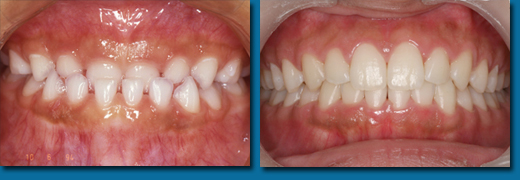

歯並びが悪くなってから治療することを歯列矯正といいますが、乳歯の頃から出てくる歯並びが悪くなる兆候を早期に発見しそれを改善しながらきれいな歯並びの永久歯にしていくことを咬合育成といいます。専門的には歯列矯正と咬合育成は別の物と区別されています。咬合育成は歯並びの予防と考えられ当医院では積極的に取り組み、多くの歯並びの良い子供が育っています。写真の左は乳歯の時、右が永久歯になった時のものです。